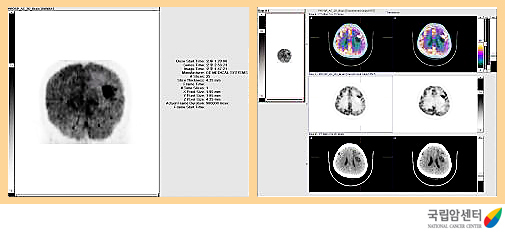

교모세포종의 양전자방출단층촬영 소견

2009.12.16